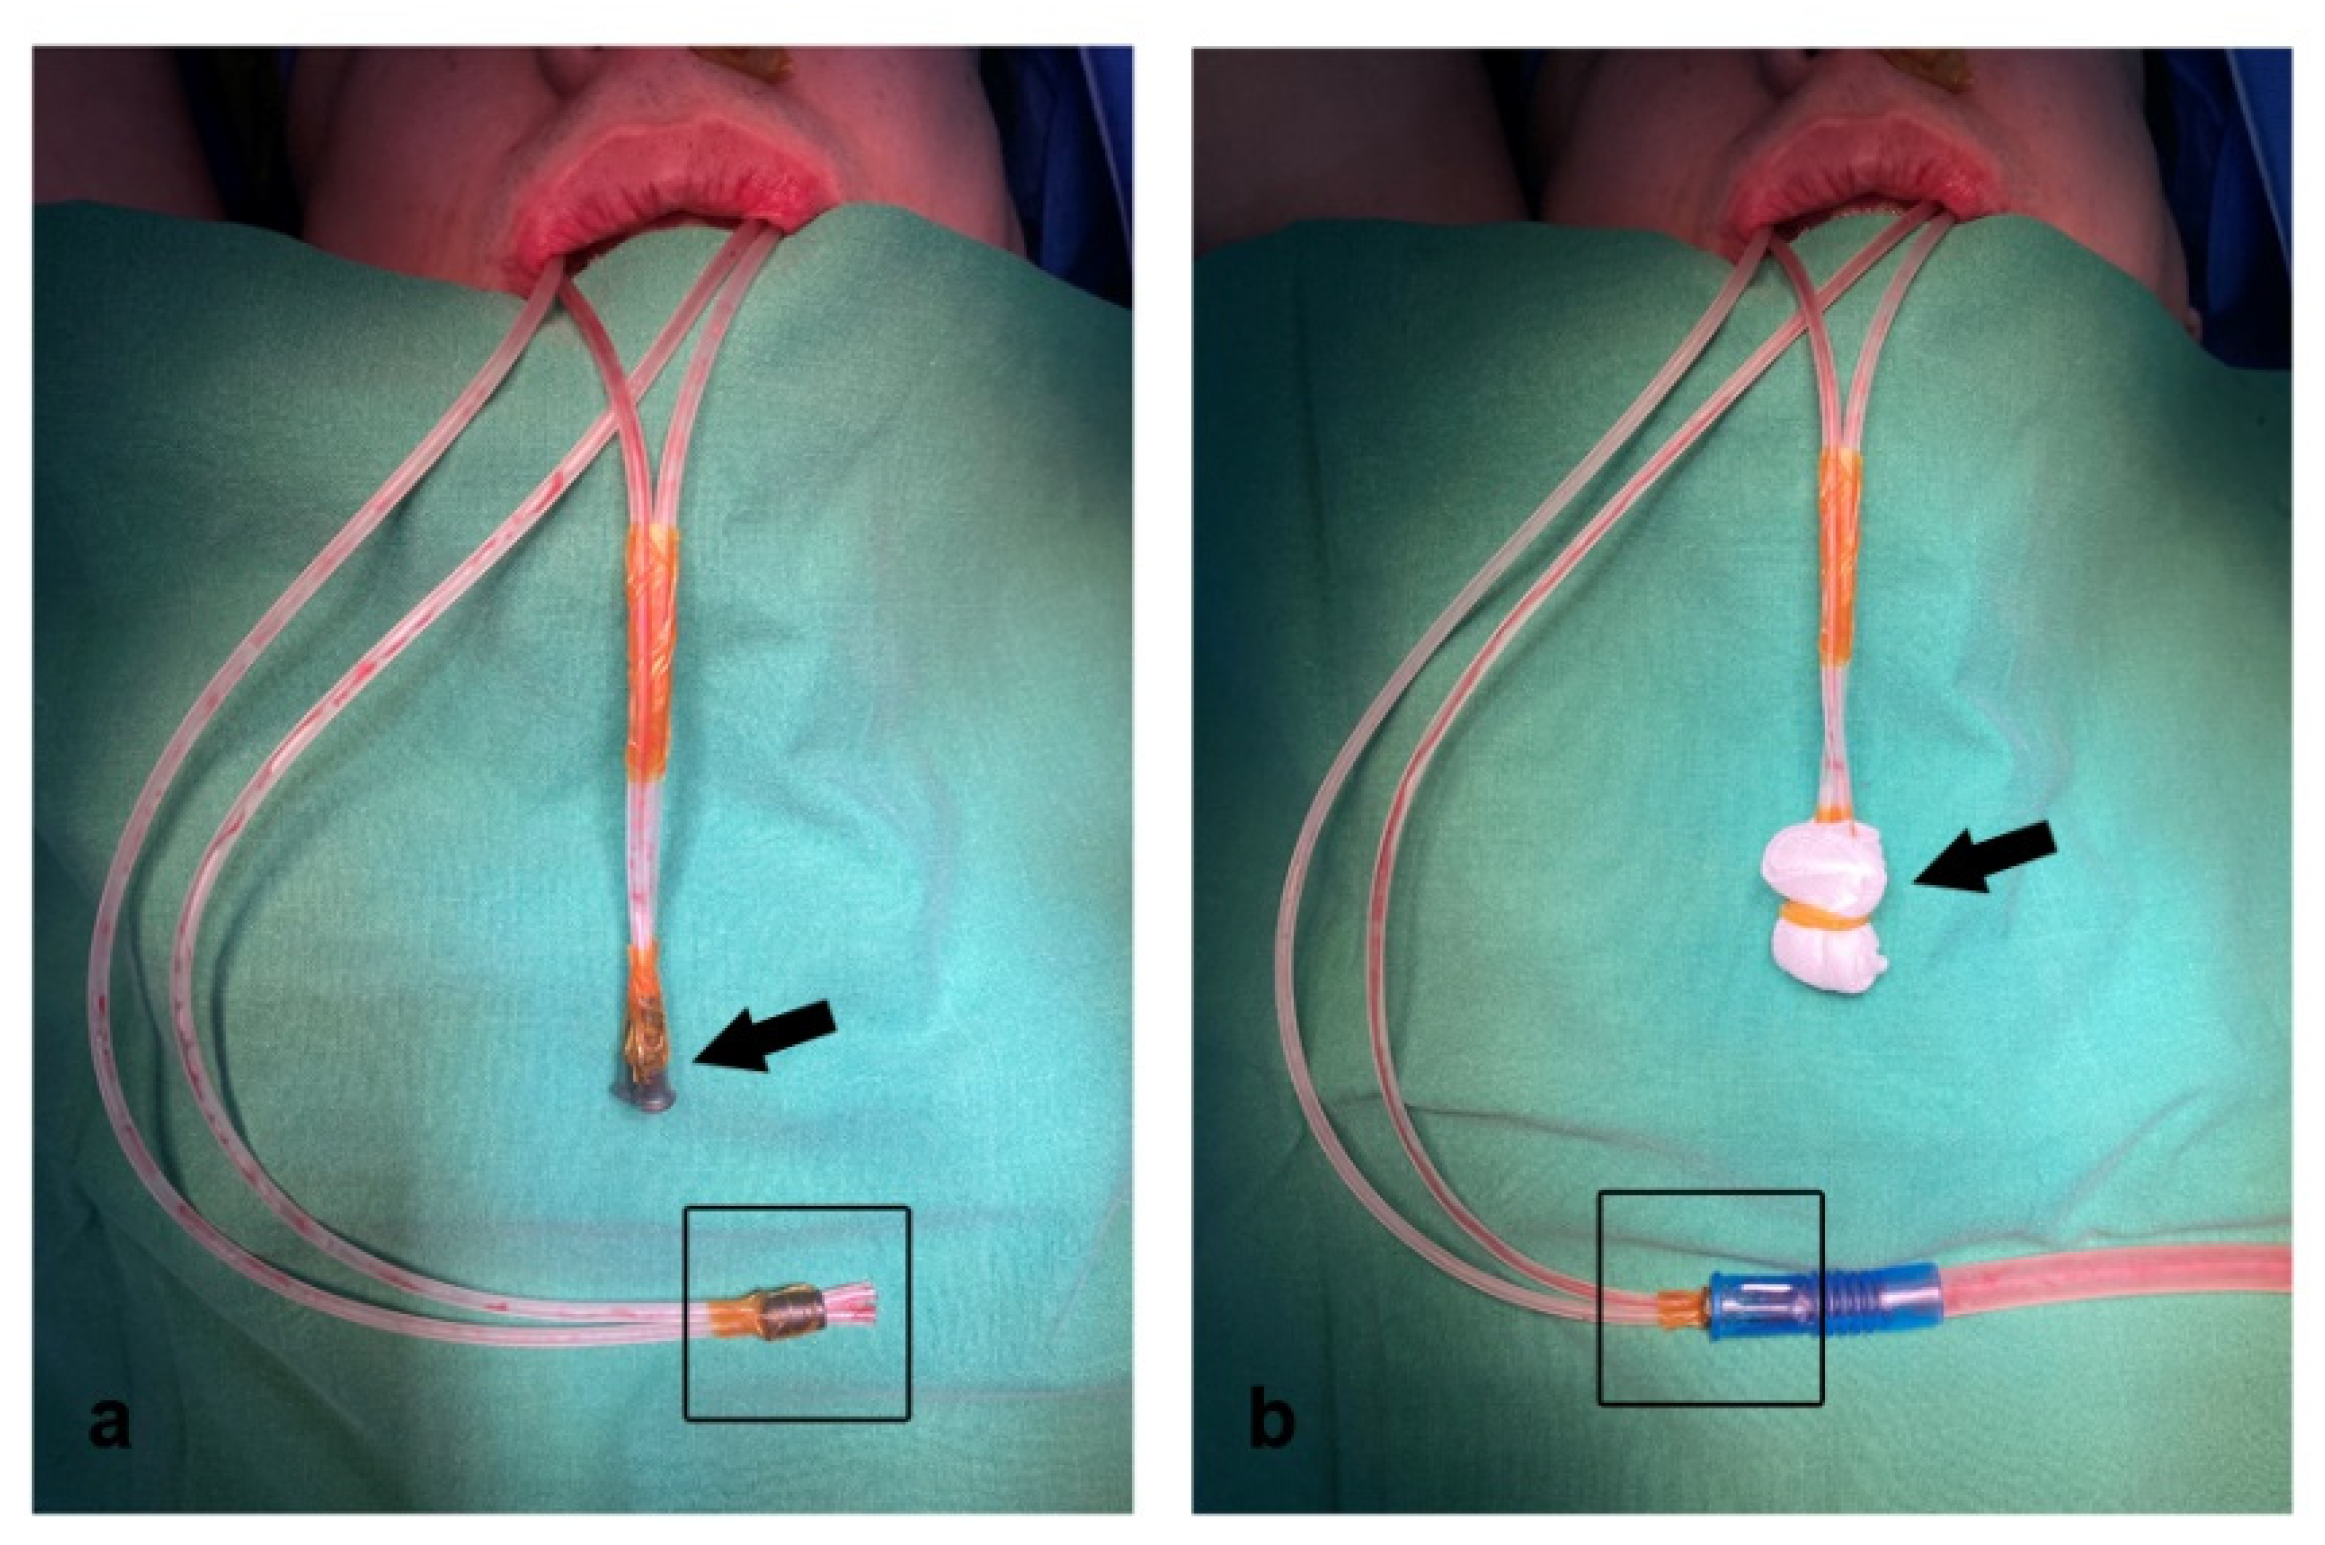

2. Materials and Methods